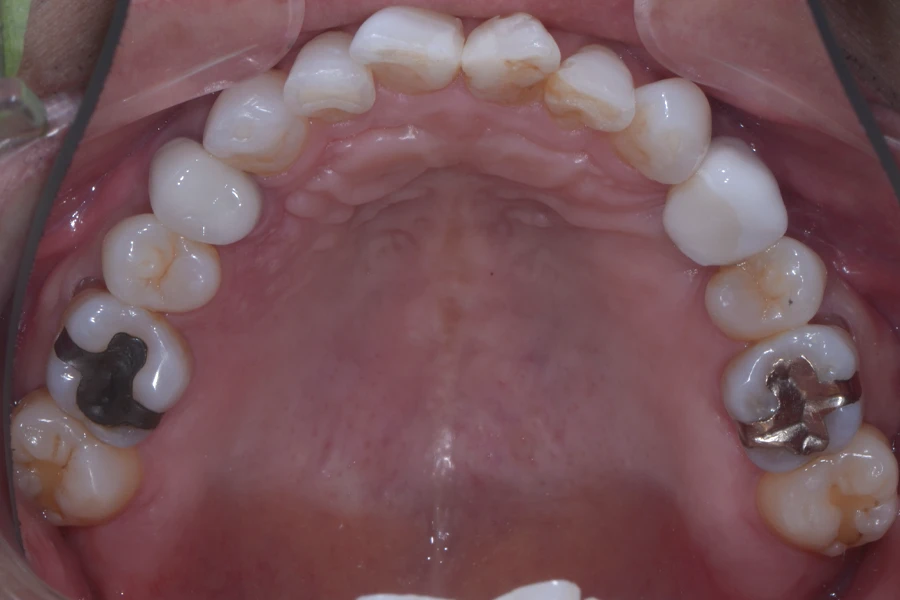

【50代男性】

インプラント治療後に

前歯の形を良くしたい

【矯正歯科治療】

治療前

主訴 インプラント治療後に前歯の形を良くしたい

期間 12か月

費用 40万円(別途調整料)

治療内容 上下顎ラビアル矯正(表側矯正)

治療に伴うリスク 後戻り